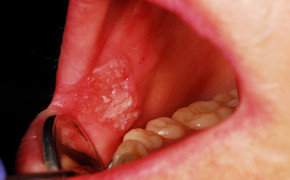

7 dấu hiệu cảnh báo ung thư miệng dễ bị bỏ qua

Khi nói đến sức khỏe răng miệng, ngay cả những triệu chứng nhỏ nhất cũng có thể cảnh báo một vấn đề sức khỏe nghiêm trọng, ví dụ như ung thư.

Triệu chứng thường gặp của ung thư miệng khá giống với những bệnh lý răng miệng khác, bạn hãy đi khám nếu có những dấu hiệu dưới đây.